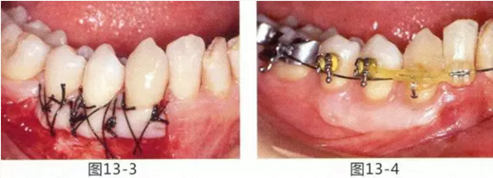

圖13-3 手術(shù)剛結(jié)束的狀態(tài)。通過(guò)骨膜縫合的褥式縫合將移植片固定,使其無(wú)法移動(dòng)。

圖13-4 手術(shù)完成2年后的狀態(tài)??谇磺巴サ玫綌U(kuò)張,即使正在進(jìn)行正畸治療,也沒(méi)有妨礙到清潔。